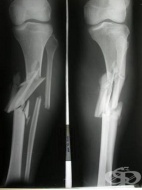

S82.7 Множествени счупвания на подбедрицата

Фрактура на костите на подбедрицата, при които една кост тибия или фибула има прекъсване на коста на...